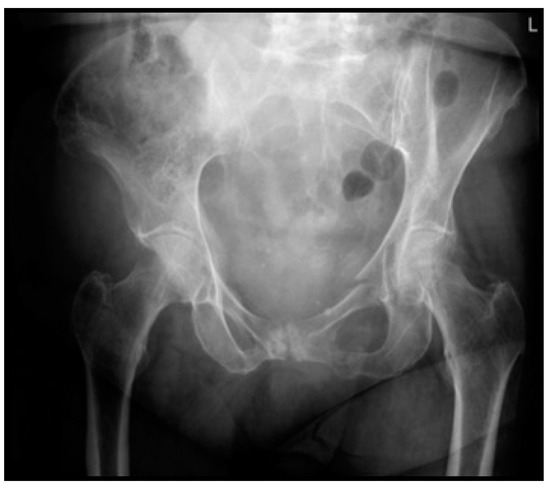

| 12. Mrs. A. is a 75-year-old, independently living ASA 2 patient. She tripped and fell at home. Plain radiographic imaging showed a superior/inferior ramus fracture on the left side. Would you, based on this information, perform a CT scan in the hospital you work at? | A. No, a CT scan has no treatment consequences B. Yes, always C. Yes, if the patient has pain on palpation of the sacrum D. Yes, if the patient is very painful during mobilization E. Otherwise, namely: |

| 13. Mrs. B. is a 77-year-old ASA 4 patient living in sheltered housing. She tripped and fell at home. Plain radiographic imaging showed a superior/inferior ramus fracture on the left side. Would you, based on this information, perform a CT scan in the hospital you work in? | A. No, a CT scan has no treatment consequences B. Yes, always C. Yes, if the patient has pain on palpation of the sacrum D. Yes, if the patient is very painful during mobilization E. Otherwise, namely: |

| 14. Mrs. C. is a 75-year-old, independently living ASA 2 patient. She fell on the street, and plain radiographic imaging showed a superior/inferior ramus fracture on the right side. She is discharged from the ER with oral painkillers. The patient comes back to your outpatient clinic after 14 days. She mobilizes with difficulty, sits in a wheelchair, walks with a four-wheel walker indoors, and uses Paracetamol and Diclofenac. A CT scan shows an LC1/FFP3c fracture. Do you think, based on this information, the patient is eligible for surgical fixation? | A. No, I do not think this is indicated and would have little impact on this patient’s outcome B. No, I think operative pelvic fixation would be too invasive for this patient C. Yes, if the patient has evident pelvic pain during a physical exam D. Yes, only if the pain did not decrease at 6 weeks follow-up E. Otherwise, namely: |

| 15. Mrs. D. is a 69-year-old, independently living ASA 3 patient with COPD Gold 3. She fell on the street, and plain radiographic imaging showed a superior/inferior ramus fracture on the right side. She is discharged from the ER with oral painkillers. The patient comes back to your outpatient clinic after 14 days. She mobilizes with difficulty, sits in a wheelchair, walks with a four-wheel walker indoors, and uses Paracetamol and Diclofenac. A CT scan shows an LC1/FFP3c fracture. Do you think, based on this information, the patient is eligible for surgical fixation? | A. No, I do not think this is indicated and would have little impact on this patient’s outcome B. No, I think operative pelvic fixation would be too invasive for this patient C. Yes, if the patient has evident pelvic pain during a physical exam D. Yes, only if the pain did not decrease at 6 weeks follow-up E. Otherwise, namely: |

| 16. Mrs. E is an 81-year-old ASA 3 patient. She fell on the street, and plain radiographic imaging showed a superior/inferior ramus fracture on the right side. She is admitted to the nursing ward and has difficulty turning in bed. Transfer from bed to toilet chair is possible. She uses Paracetamol, Diclofenac and Oxynorm. A CT scan shows an LC1/FFP3c fracture. Do you think, based on this information, the patient is eligible for surgical fixation? | A. No, I do not think this is indicated and would have little impact on this patient’s outcome B. No, I think operative pelvic fixation would be too invasive for this patient C. Yes, if the patient has evident pelvic pain during a physical exam D. Yes, only if the pain did not decrease at 6 weeks follow-up E. Otherwise, namely: |